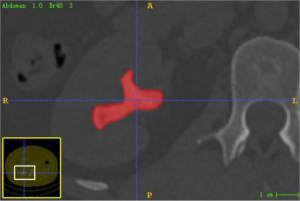

CT image acquisition and stone segmentation

Thin-layer (1.0 mm), axial, unenhanced urological CT images of the enrolled cases were exported in DICOM format from the Picture Archiving and Communication System (PACS). A radiologist with >10 years of diagnostic experience imported the CT images one by one into the 3D image segmentation software package ITK-SNAP (Version 3.8.0-Beta, University of Pennsylvania), drew the regions of interest (ROI) layer by layer, and saved the segmented images in nii.gz format (Figure 2). ITK-SNAP software comes with image registration function, which can automatically adjust the image gray level, that is, the standardization of the image. Stone segmentation principle: drawing on the axial image; ROI is delineated along the stone edge, trying to include the stone as a whole and avoiding the inclusion of surrounding renal tissue, blood vessels, fat or image artifacts to ensure data reliability.